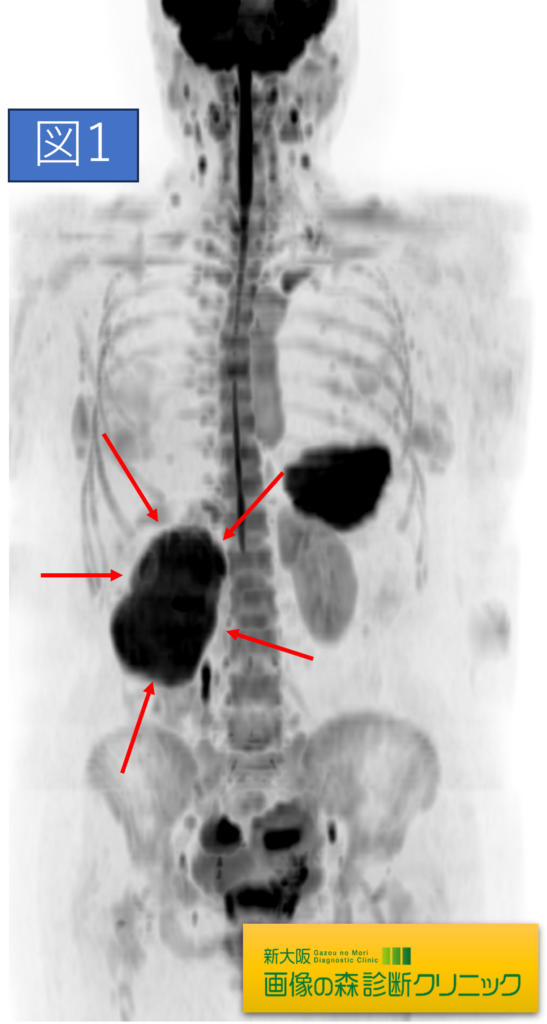

DWIBS_MRI画像(MIP像)

症例画像から図1~図4は腎臓癌の画像です。矢印は腎臓癌を示します。図1・図2はDWIBS_MRIの画像です。DWIBS_MRIは、頚部~骨盤までの広範囲の癌検索を目的としており、癌の疑いのある臓器はこの画像の場合、黒く描出されます。(脳や脾臓も黒く見えますが、これらの部位は他の部位より黒く描出されやすいので、その他の撮影画像と比較することで評価されます)図3・図4は造影剤を使用し腎臓に焦点をあて検査した画像です。